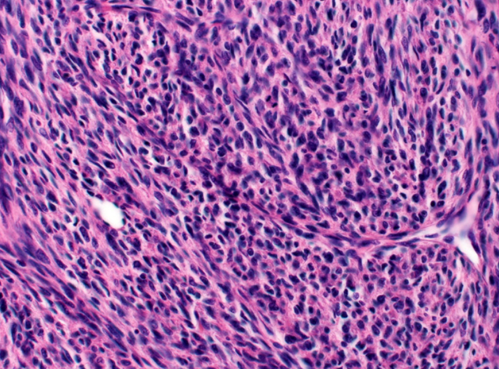

Intestinal carcinoids can cause diarrhea and are often associated with additional symptoms such as flushing, wheezing, and vascular telangiectasia when they metastasize. Histopathology is typified by insular and trabecular masses of monotonous small round cells with peripheral palisading, finely granular cytoplasm, small nucleoli, and salt and pepper chromatin.